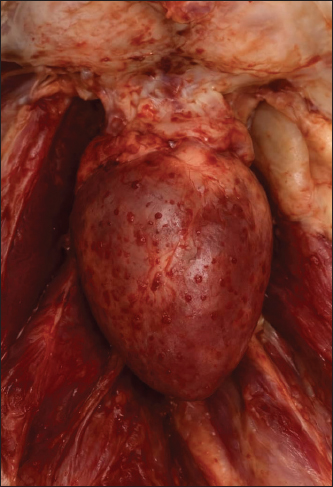

Clinical signs were nonspecific: depression, ruffled feathers, inappetence, and recumbency—findings typical of metabolic disturbances and toxic exposures (Al-Mayah and Al-Mayah, 2018). Gross pathological findings included the following: Intoxication with ammonium chloride can induce hepatic congestion, renal swelling, and muscular hemorrhages due to tissue acidosis (Figs. 14) (Farrag et al.,2015 and Abbas et al., 2017).

Fig. 3. Enlarged, dark reddish congested liver.

Fig. 4. Enlarged kidneys with marked congestion and swelling.